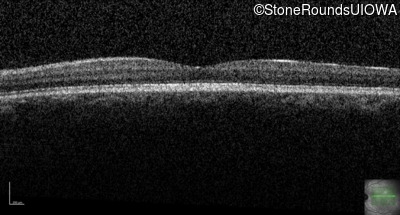

Congenital Stationary Synaptic Dysfunction (IA2g)

Congenital Stationary Synaptic Dysfunction (IA2g)

| Congenital Stationary Synaptic Dysfunction | CABP4 | Arg49Stop CGA>TGA | IVS1+1 G>T | AR |